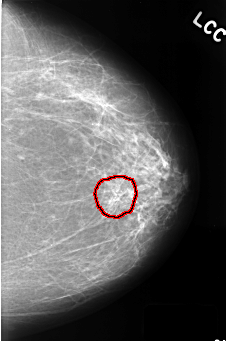

ics_version 1.0 filename C-0390-1 DATE_OF_STUDY 16 5 1996 PATIENT_AGE 66 FILM FILM_TYPE REGULAR DENSITY 2 DATE_DIGITIZED 9 11 1998 DIGITIZER LUMISYS LASER SEQUENCE LEFT_CC LINES 4424 PIXELS_PER_LINE 2928 BITS_PER_PIXEL 12 RESOLUTION 50 OVERLAY LEFT_MLO LINES 4472 PIXELS_PER_LINE 2952 BITS_PER_PIXEL 12 RESOLUTION 50 OVERLAY RIGHT_CC LINES 4520 PIXELS_PER_LINE 2960 BITS_PER_PIXEL 12 RESOLUTION 50 OVERLAY RIGHT_MLO LINES 4560 PIXELS_PER_LINE 2904 BITS_PER_PIXEL 12 RESOLUTION 50 OVERLAY |

FILE: C_0390_1.LEFT_CC.OVERLAY TOTAL_ABNORMALITIES 1 ABNORMALITY 1 LESION_TYPE CALCIFICATION TYPE PLEOMORPHIC DISTRIBUTION CLUSTERED ASSESSMENT 4 SUBTLETY 4 PATHOLOGY BENIGN TOTAL_OUTLINES 1 BOUNDARY |